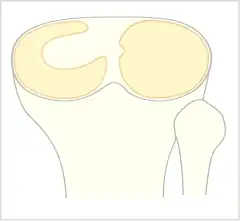

Discoid meniscus is a rare human anatomic variant that usually affects the lateral meniscus of the knee. Usually a person with this anomaly has no complaints; however, it may present as pain, swelling, or a snapping sound heard from the affected knee. Strong suggestive findings on magnetic resonance imaging includes a thickened meniscal body seen on more than two contiguous sagittal slices.

The Watanabe classification of discoid lateral meniscus is: (A) Incomplete, (B) Complete, and C) Wrisberg-ligament variant [2] Normally, the meniscus is a thin crescent-shaped piece of cartilage that lies between the weight bearing joint surfaces of the femur and the tibia. It is attached to the lining of the knee joint along its periphery and serves to absorb about a third of the impact load that the joint cartilage surface sees and also provides some degree of stabilization for the knee. There are two menisci in the knee joint, with one on the outside (away from midline) being the lateral meniscus and the inner one (towards midline) the medial meniscus. A discoid meniscus is a congenital anomaly of the knee found in 3% of the population (up to 15% in Asia). It typically affects the lateral meniscus and may be found bilaterally (20%). Instead of the narrow crescent shape, as seen in a normal meniscus above, a discoid meniscus is thickened, and has a fuller crescent shape. In addition, a discoid meniscus does not taper as much towards the center of the joint and is shaped like a disc. The thickness of the meniscus, its diminished vascular blood supply, and in some instances, weak capsular attachment, makes it more prone to tears compared to a normal meniscus. The anomaly in itself is asymptomatic; however, a tear of the meniscus can result in pain, swelling, and snapping in the affected knee. The orthopedic classification of discoid menisci includes: complete, incomplete or Wrisberg-ligament types as depicted here. Coverage of the lateral tibial plateau determines the designation of complete or incomplete. The Wrisberg-ligament type has an abnormal posterior attachment by attaching to part of the posterior cruciate ligament.